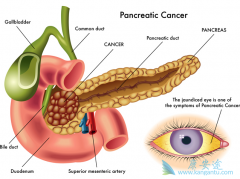

2018年2月,我国国家癌症中心发布了最新中国癌症统计数据。结果显示, 胰腺癌 位列中国城市男性恶性肿瘤发病率的第8位以及大城市(北京、上海)人群恶性肿瘤死亡率的第5位。 2014年我国胰腺癌新发约9.2万例,死亡约8.1万例。而2014年全年新发癌症患 ...

局部进展期 胰腺癌 的治疗方案。通常情况下,局部进展期胰腺癌的患者在一开始并不适合手术治疗,只有少数体能较好的患者接受一定治疗后肿瘤转变为可切除才考虑手术治疗。化疗是局部进展期胰腺癌主要的治疗方法,依据患者的体能状态开展化疗。一线治疗时 ...

胰腺是身体内非常重要器官,如果患者和家属有心留意,肯定能发现不少胰腺疾病致死的报道。同时,胰腺的解剖位置隐蔽,早期癌症难以发现,导致很多患者确诊时就是局部晚期或转移性 胰腺癌 。 晚期癌症本身就很危险了,更何况是胰腺癌。其次是医疗因素 ...